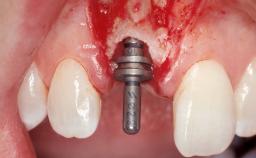

| # of Implants | 1 |

| Type of Implants | Two-Piece |

| Soft Tissue Grafting | Simultaneous |

| Abutment Type | Customized |

| Placement Protocol | Early or late implant placement |

| Bone Volume | Deficient horizontally, requiring prior grafting |